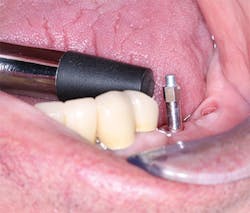

Figure 3: What resistance will this osteotomy provide to implant placement? Assuming the clinician has set the torque of the implant placement motor correctly, and the implant goes into the bone with the amount of torque at which the motor is set, the clinician may make a good estimation about the timing for implant loading.

Figure 4: On screwing the implant into place, bone density or lack of it is obvious.